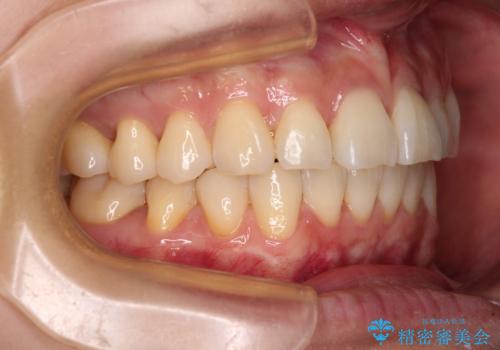

- 奥歯の咬み合わせと、上下前歯の隙間を気にして来院された患者様です。

上顎の歯列全体が、下顎歯列に対して前方に位置しており、その影響で上顎前歯がやや前方に突出している状態でした。

横顔の印象から、抜歯をして積極的に口元を引っ込める必要はなかったため、アンカースクリューを用いて上顎歯列全体を後方に移動させることとしました。

奥歯の咬み合わせは理想的な状態に改善され、その結果として上下歯列もバランスの良い位置に収めることができました。

若干ではあるものの上顎前歯を内側に移動させることができ、以前よりも口が閉じやすいと感じるようになりました。